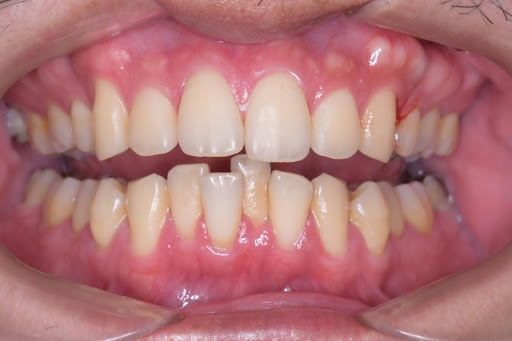

こちらはインビザラインフルプランの術前の写真です。

これがその術後の症例写真です。

フルプランのためかなり全体的に綺麗になりました。